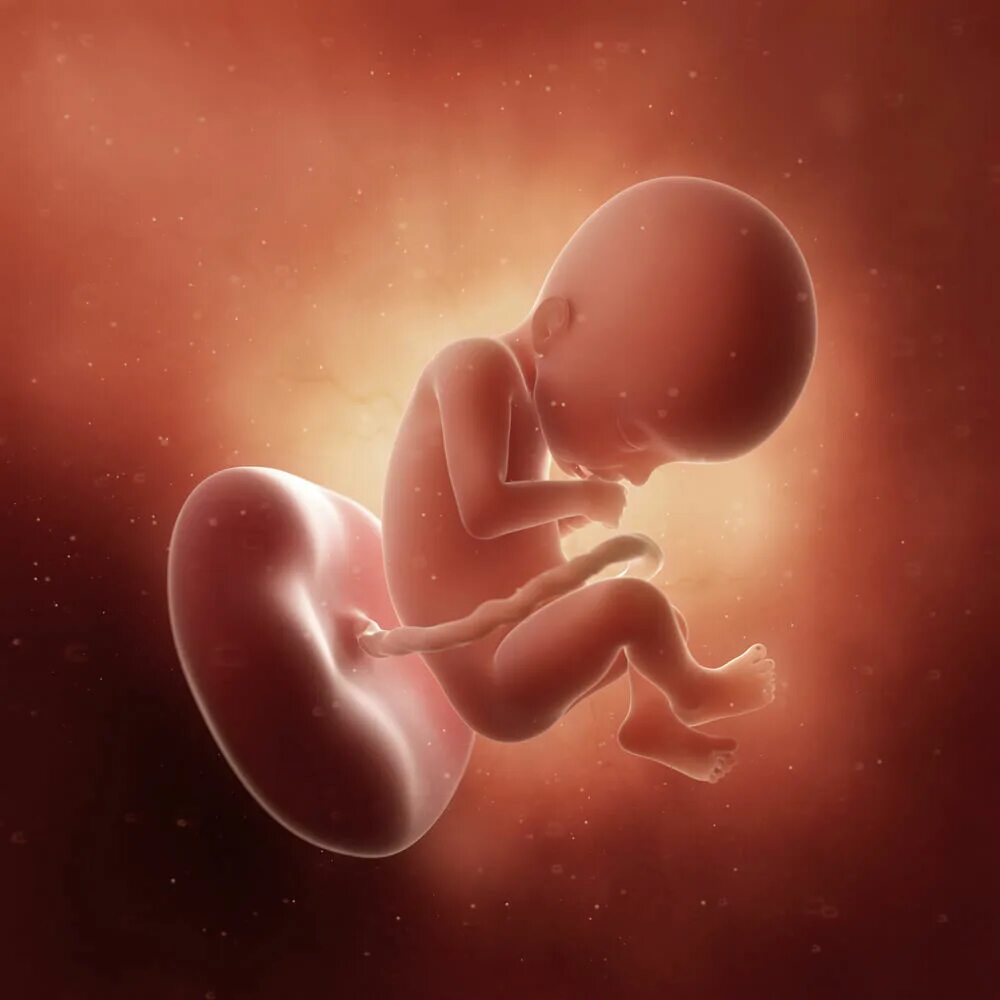

Как выглядит ребенок в 22 недели